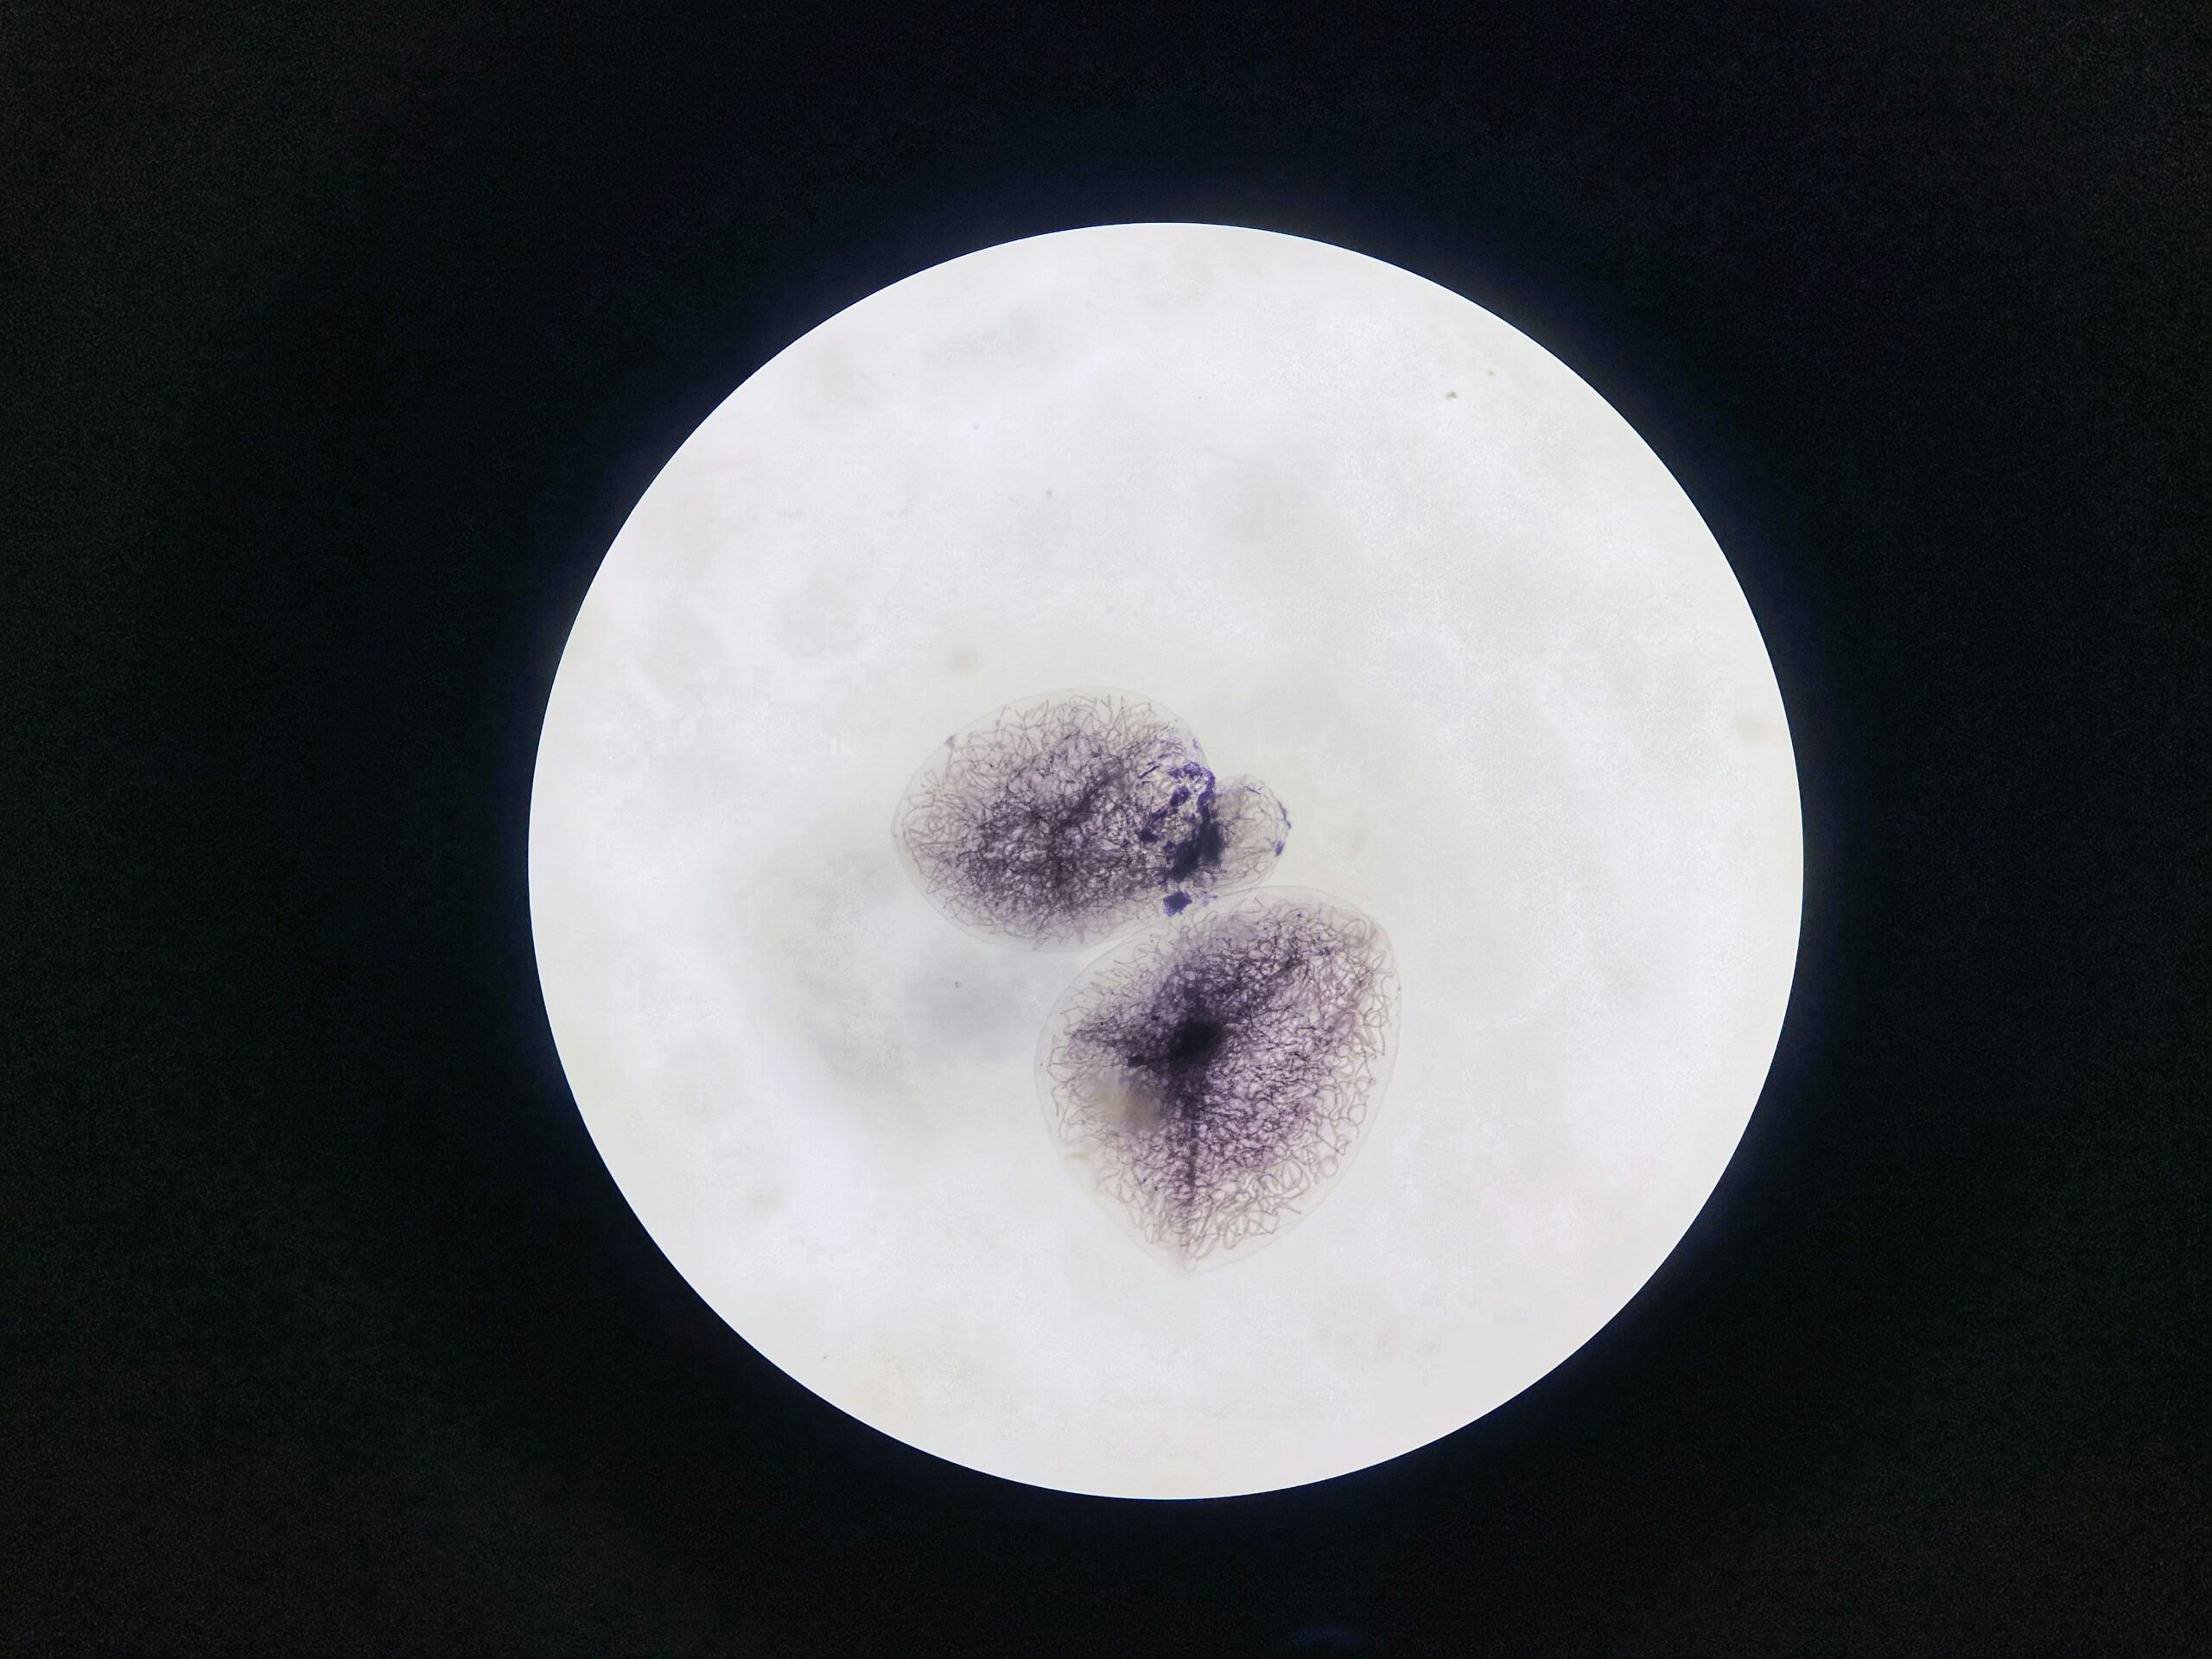

Even highly graded and genetically tested embryos (such as those screened with PGT-A) can fail to implant because implantation requires a highly orchestrated interaction between embryo and uterus. Many embryos, even those that look healthy under the microscope, have chromosomal abnormalities that prevent implantation or early development. Research shows that most embryos naturally stop developing shortly after fertilization due to spontaneous errors in early cell division.